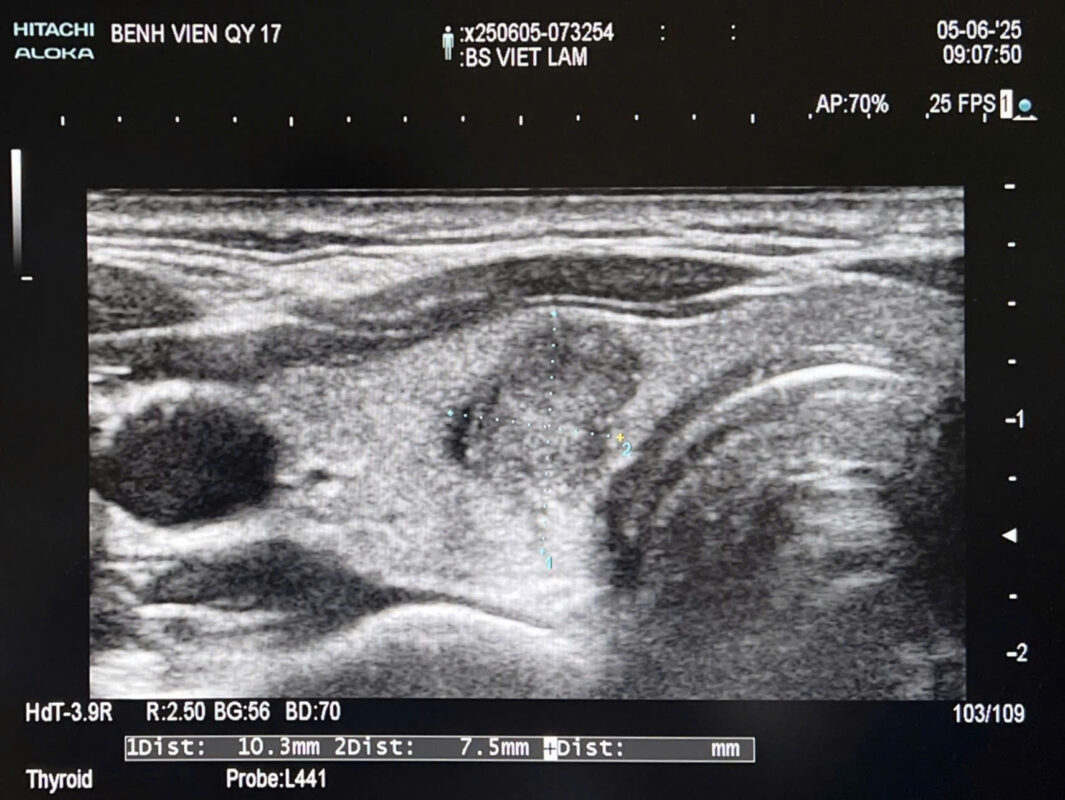

💡 Tổng Quan về Ung Thư Tuyến Giáp Ung thư tuyến giáp là một trong những bệnh lý ung thư nội tiết phổ biến nhất, có thể gặp ở mọi lứa tuổi nhưng chủ yếu ở phụ nữ và những người từ 20 đến 60 tuổi. Phát hiện sớm và chẩn đoán chính xác rất